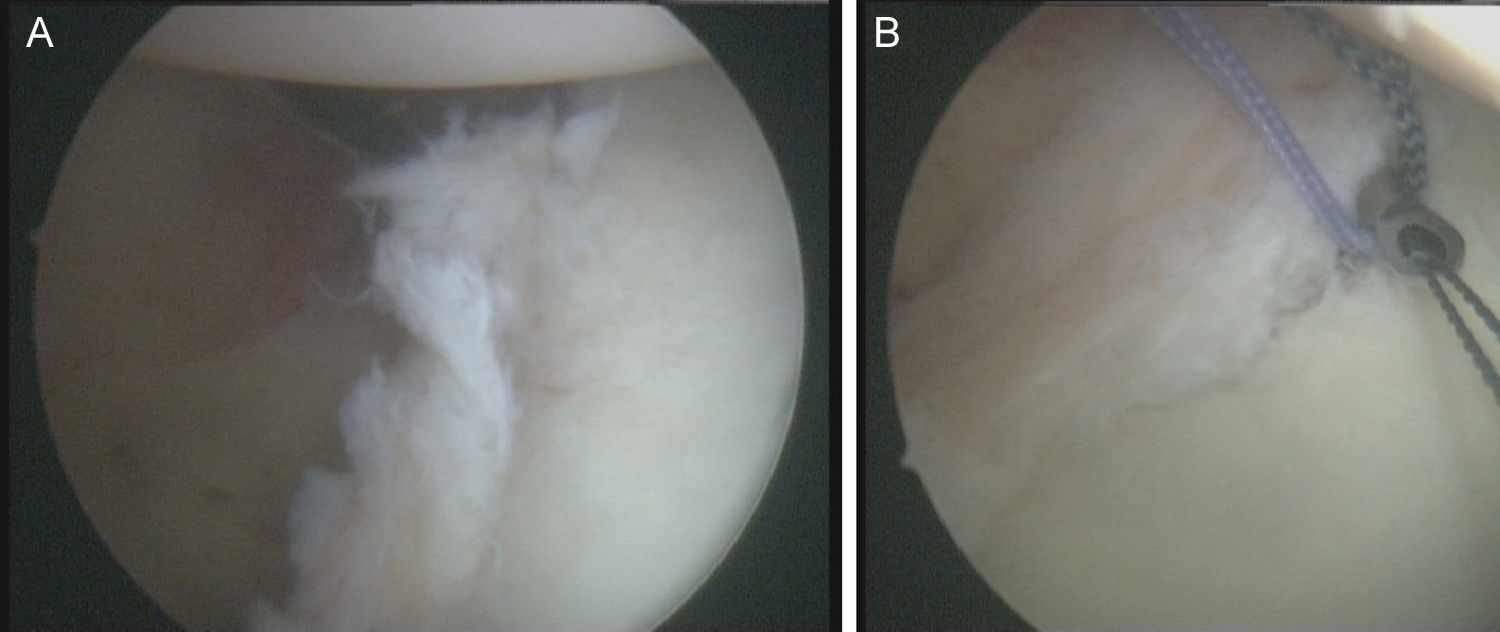

Técnica quirúrgicaBajo anestesia general y locorregional (bloqueo interescalénico), se intenta reducir el hombro de forma cerrada. En caso de no conseguirlo se coloca al paciente en decúbito lateral con tracción de unos 5kg y, siguiendo la técnica descrita por Verma5, se introduce un «Wissinger» por el portal posterior estándar, el que empleamos para la artroscopia de hombro. Con el «Wissinger» a través del portal realizamos tracción de la cabeza humeral hacia lateral, apoyándonos en la cápsula y en la parte posterior del manguito, no en el hueso. Habitualmente con esta maniobra conseguimos introducir la cabeza humeral en la glenoides y podemos pasar a realizar la artroscopia de hombro. En caso de no conseguir una reducción, pasaríamos a realizar una reducción abierta con el paciente en posición de silla de playa y con una vía de abordaje anterior al hombro. Con el hombro reducido se realiza la artroscopia de hombro. Se emplean los portales posterior, anterosuperolateral, anterior, portal de Wilmington y portal posteroinferior. Se estudia la lesión de Hill-Sachs inverso, la relación con el tendón del subescapular y la lesión del labrum posterior (fig. 2, figs. 3 y 4), el resto del labrum y el manguito de los rotadores. Hay que limpiar bien la articulación, extirpar todo el tejido fibroso, liberar el labrum posterior de las adherencias a la glena, preparar el lecho óseo de la glena antes de colocar los implantes (en el caso 1 se emplearon 2 implantes Lupine BR [DePuy Mitek, Raynham, MA], y el caso 2 con un Gryphon BR [DePuy Mitek, Raynham, MA] cargado con doble sutura), realizar la reconstrucción capsulolabral con un pasador directo o indirecto, anudar y cortar las suturas. Una vez reparadas las lesiones soltamos el brazo del sistema de tracción y comprobamos la relación de la cabeza humeral, del defecto óseo anterior con la glenoides, al hacer rotaciones del hombro (sobre todo si hay riesgo de «enganche» con la rotación interna), y decidimos si fijamos el tendón del subescapular en el defecto óseo humeral anterior, tal y como describió Krackhardt6.

No es estrictamente necesario que reproduzcamos un enganche de la lesión de Hill-Sachs inversa para decidir realizar el remplissage inverso. Con la óptica en el portal anterosuperolateral liberamos el tendón del subescapular, su cara anterior y posterior. Preparamos el lecho óseo de la cabeza humeral, extirpando todo el tejido fibroso de la lesión de Hill-Sachs inversa, con el sinoviotomo, la fresa de hueso o periostotomos, hasta obtener hueso sangrante. Entonces desde el portal anterior, insertamos los implante en el defecto óseo (en el caso 1 un 5,5 Healix BR [DePuy Mitek, Raynham, MA] con 2 suturas UHMWPE [Orthocord; DePuy Mitek]) en el tercio superior y en la zona más medial del defecto (fig. 5), y en el caso 2 insertamos 2 Gryphon BR Healix BR (DePuy Mitek, Raynham, MA) con 2 suturas UHMWPE (Orthocord; DePuy Mitek), uno inferior y otro superior en la zona más medial del defecto óseo. Recuperaremos las suturas desde un portal anterosuperior accesorio y con una pinza para atravesar el tendón (Penetratror DePuy Mitek, Raynham, MA) a través del portal anterior, atravesamos el tendón del subescapular y recuperamos las suturas. Daremos puntos colchoneros, uno inferior y otro superior, para conseguir un buen contacto del tendón con el hueso, separando los puntos entre 1 y 2cm (fig. 6). Podemos ayudarnos con un empujanudos a través del portal anterosuperior accesorio para el manejo y recuperación de las suturas, acercándolas a la boca de la pinza penetrator, tratando de no mover en exceso la pinza una vez atravesado el tendón, para evitar lesionar el tendón y el cartílago. Manteniendo el brazo en 35-40° de rotación interna anudamos primero el punto inferior y luego el superior (figs. 7 y 8).

Caso 1, hombro derecho. A. Vista desde el portal ASL de la lesión de Hill-Sachs inversa con el implante en el tercio medial del defecto óseo. B. Imagen después de hacer los nudos; podemos ver el tendón del subescapular rellenando parcialmente el defecto óseo de la cabeza humeral, con la cabeza centrada en la cavidad.